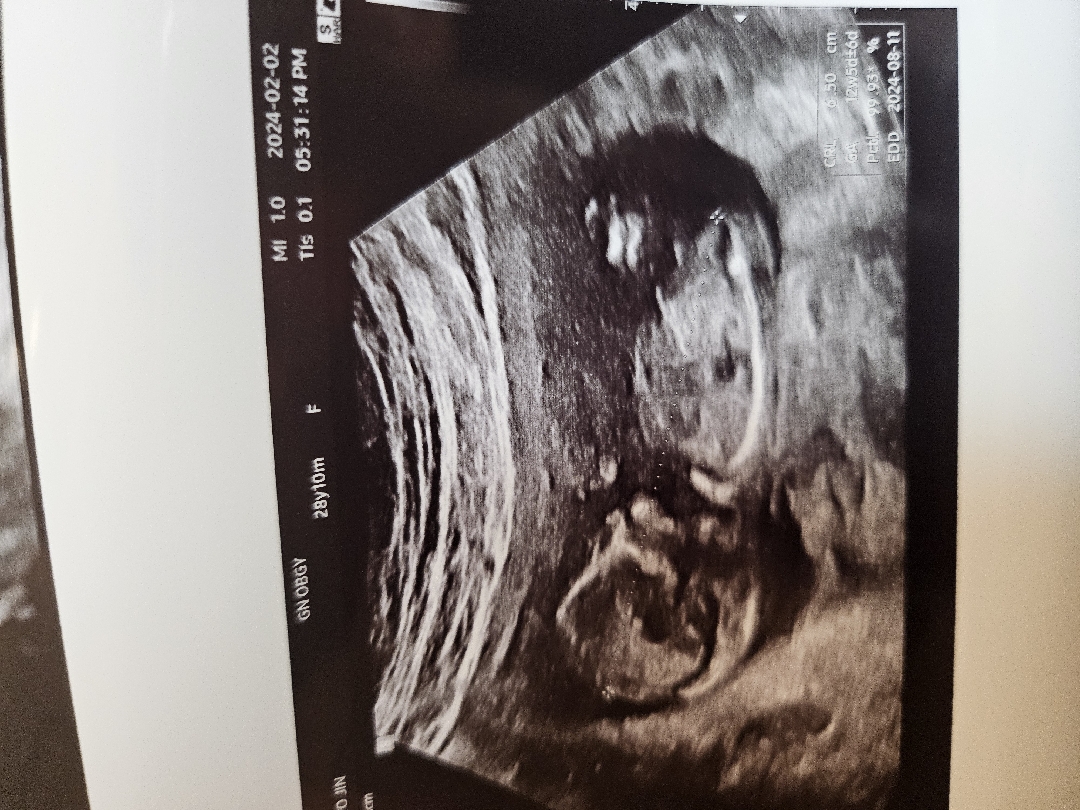

12주 각도법 봐주실 수 있나요!

각도법 사진은 병원에서 안된다고 하고 혹시 이 사진으로도 구별 가능할까요 ㅠㅠ